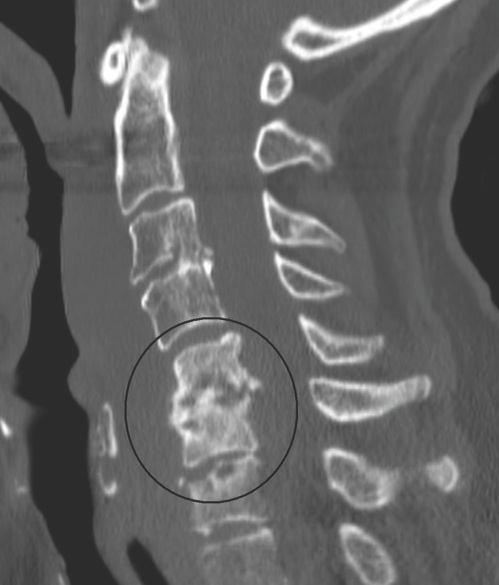

Orthopedics

10/17/2014

Leigh Ann Lather, MD

A previously healthy 5-year-old boy presented for evaluation of an abnormal gait.